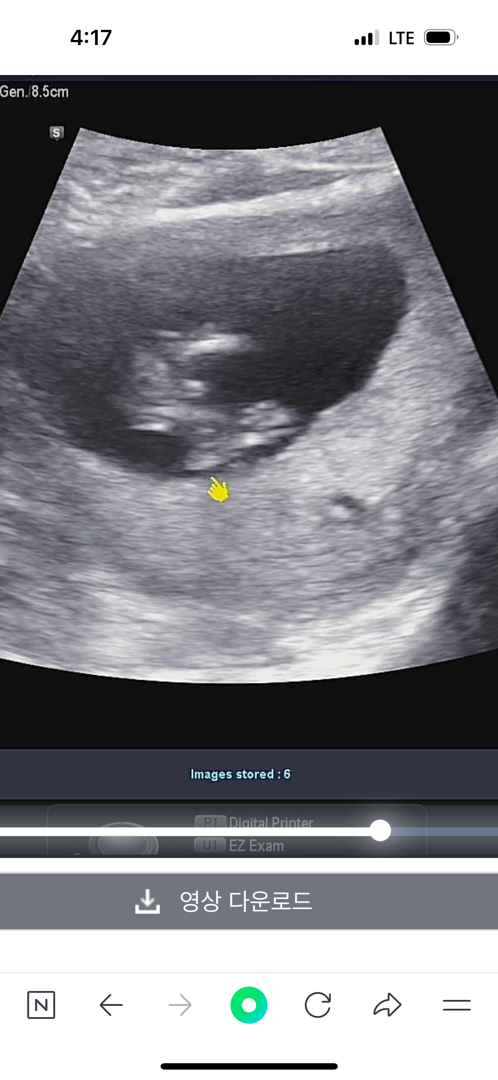

사진이 두장은안들어가나봐요 ㅠㅠ 입체랑 햇을때 아가가 다리를꼬고잇다가 풀엇는데 가운데 뭐가잇는것같다고 의사쌤이 그러더라구요 !! 이럴땐 거의 아들이라면서 애매하게 아들이라던데 ㅠㅠ 한번봐쥬세용

혹시 몇주차세요?! 저도 조금전에 사진 올렸는데 저희 애기랑 비슷한 것 같아서요!! 저도 의사샘이 아들 예측 하셨어요!!

저는12주6일입니나 ㅎㅎ